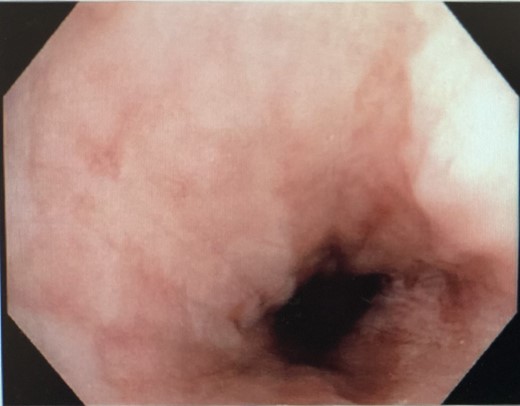

He was commenced on high-dose PPI, IV Antibiotics and analgesia. Emergency gastroscopy showed middle third of esophagus consistent with esophagitis and circumferential ischemia/necrosis in distal esophagus 27–34 cm (Fig. 6). Mucosal biopsies taken revealed ulcerated squamocolumnar mucosa with necrosis and inflammation. No CMV inclusions were identified.